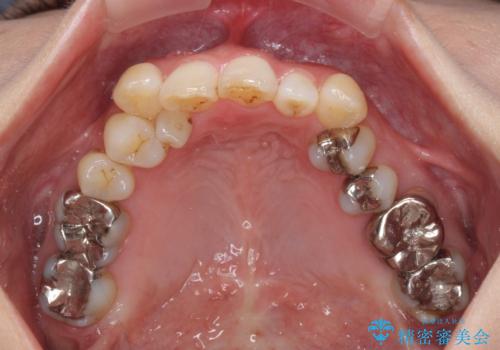

- 前歯の反対咬合を気にして来院された患者様です。

上顎骨の幅が下顎骨よりも小さいので、拡大装置により骨幅を広げて上下関係を改善すると同時にワイヤー矯正で反対咬合の改善を図り、その後インビザラインにて歯並びを整えることとしました。

上顎前歯の矮小歯は矯正治療の途中でオールセラミッククラウンを装着し、左右のバランスを整えることとしました。

急速拡大装置の使用により奥歯の咬み合わせが劇的に変わり、その変化を利用して反対咬合を改善することができました。

治療期間中は奥歯が咬み合わず、食事が取りにくいなどの不都合がありましたが、最終的にはきれいに整えることができました。